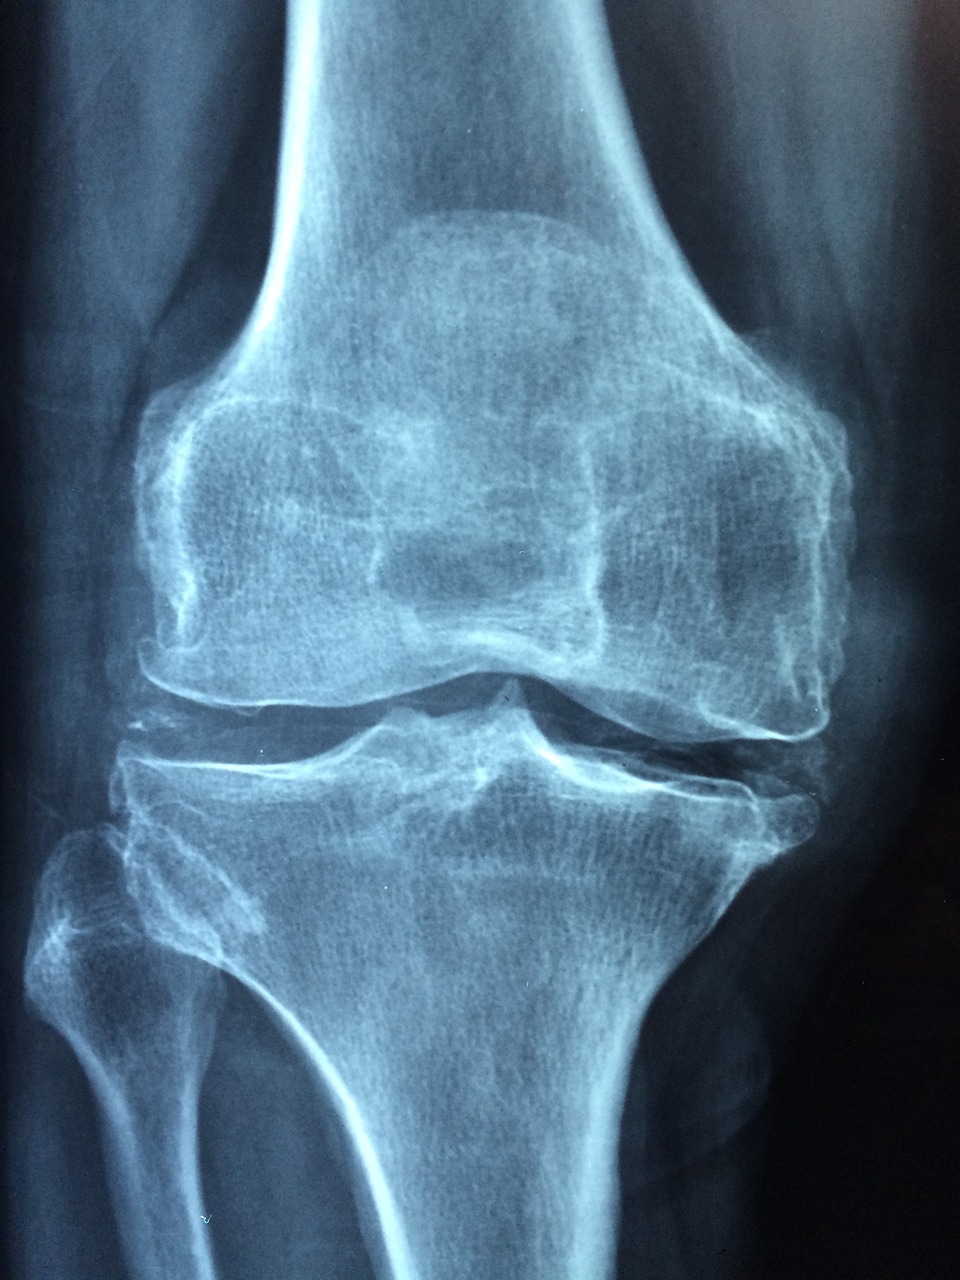

골다공증, 그거 뼈가 약해져서 골절 위험이 커지는 거죠? 요새 의사들이 치료법 찾기 위해 엄청나게 분주하더라고요. 그중에 진짜 신박한 방법 있나 한번 살펴볼까요?